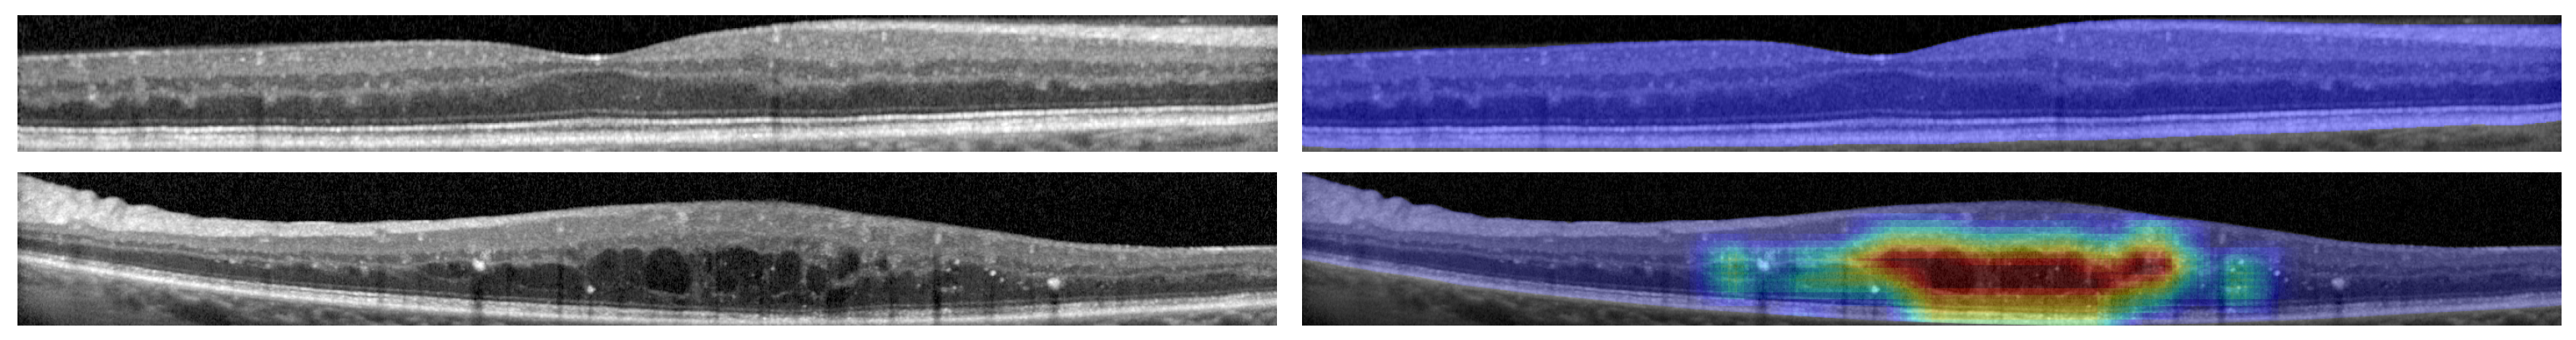

The network was trained using a base dataset of 3247 samples from two different representative OCT capture devices, increased by means of data augmentation. Additionally, the training of the network was done by using an automated control of the learning rate depending on the validation results, and stopped by means of an early-stopping criteria that detects when the training quality has stagnated. To further study the capabilities of our system, the training process was repeated 50 times, randomly distributing the training and validation datasets and recalculating the data augmentation procedure. After all the repetitions, the system attained a satisfactory mean test accuracy of 97.45% ± 0.7611 and a mean area under the ROC curve (AUC) of 0.9961 ± 0.0029. Regarding maps, as shown in Figure 1 and Figure 2, the DenseNet architecture is able to successfully represent both pathological and healthy regions in different representative devices of the domain.

Figure 1.

Results from a Spectralis OCT device from Heidelberg Engineering, including a healthy and a pathological example.